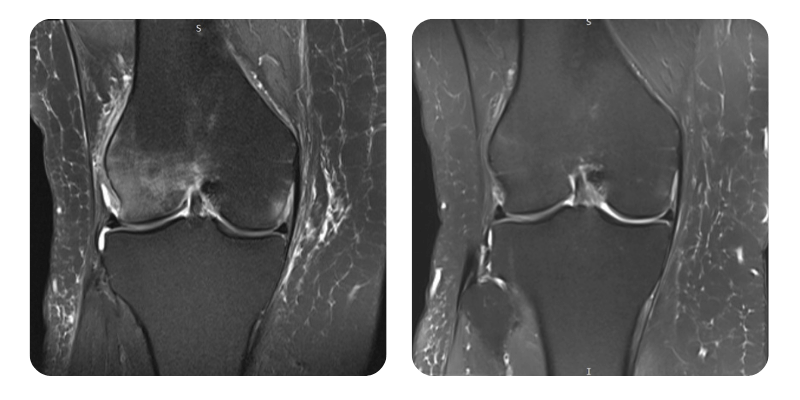

Előtte

Utána

S.M.S., 58 éves – Külső jobb combcsonti condylus nekrózisa/ödémája

Diagnózis: Külső jobb combcsonti condylus nekrózisa/ödémája, korábbi pitvarfibrilláció ablatio után jelenleg sinusritmusban, HTA, divertikulózis.

Terápiás beavatkozások: 20 alkalom hiperbár oxigénterápia.

Lefolyás: MRI-vizsgálaton kb. 90%-os ödémacsökkenés figyelhető meg.